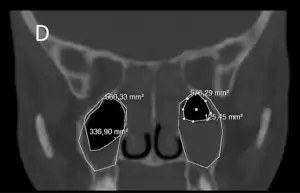

![]() Radiografía que muestra congestión de orificio nasal maxilar izquierdo indicado por una flecha. | ||

En casos con sospecha de complicaciones, que son excepcionales, se pueden realizar exámenes vídeo-endoscópicos, así como un TAC (tomografía axial computarizada). Hay que destacar que la utilización exclusiva de los rayos X para el diagnóstico de las sinusopatías está desaconsejada, debido a la alta tasa de fallos que este examen presenta para los senos faciales, incluyendo falsos positivos.